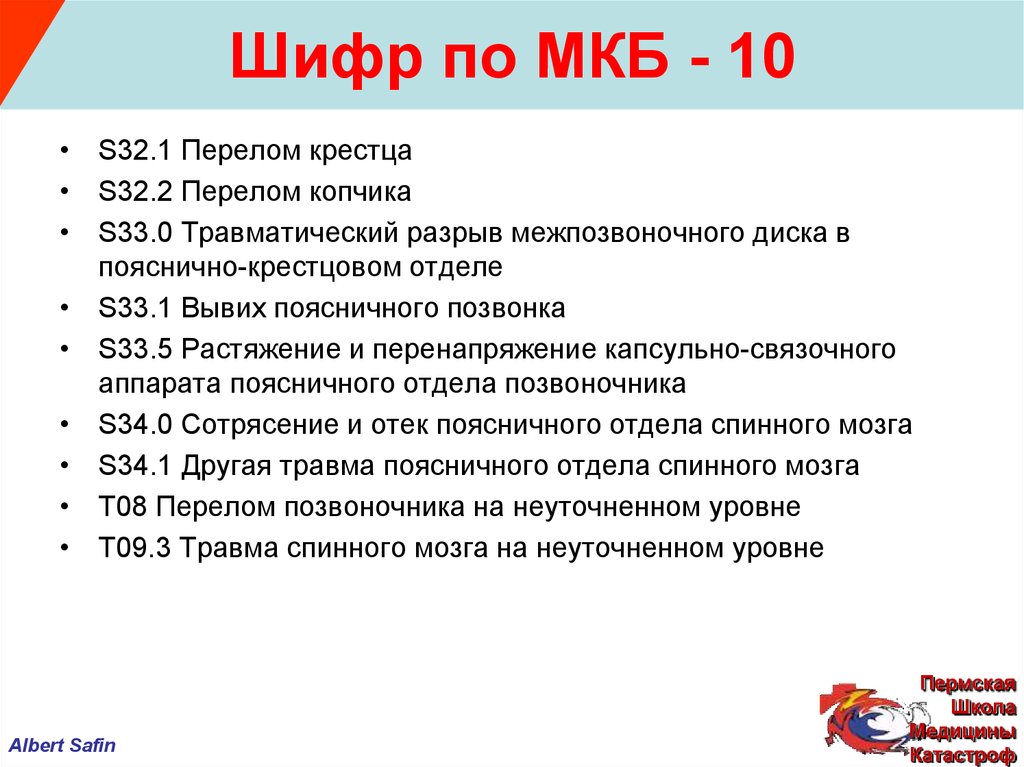

Код мкб 10 атерома головы

Код мкб 10 атерома головы 109 фото